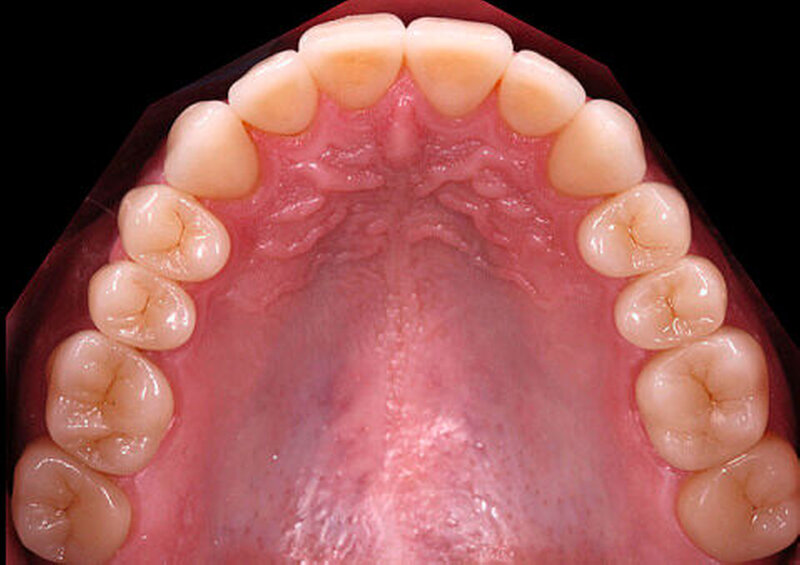

Wird die Bisslage vom Patienten beschwerdefrei akzeptiert, kann die Übertragung der Situation entweder direkt in vollkeramische Restaurationen oder zunächst in CAD/CAM-gefräste, langzeitprovisorische Repositions-Veneers oder -Onlays aus Hochleistungs- polymer – meist PMMA-Material – erfolgen (Abbildung 4). Für die Konstruktion können die Datensätze der Wax-up-Modelle verwendet werden. Die Table Tops werden gewöhnlich mittels Adhäsivtechnik auf natürlichen Zähnen und Kunststofffüllungen befestigt, können allerdings auch bei entsprechender Vorbehandlung (intra-orales Anstrahlen) auf metallischen und keramischen Restaurationsoberflächen eingesetzt werden [Bertolotti et al., 1994]. Da die neue Bisssituation nun permanent inkorporiert ist, können sich die neuronalen Bewegungsmuster besser adaptieren. Um künftig funktionelle Beschwerden nach definitiver Rekonstruktion der vertikalen Kieferrelation möglichst auszuschließen, sollte diese semipermanente Phase für etwa sechs bis zwölf Monate beibehalten werden.

Wurde die provisorische Restauration funktionell und ästhetisch vom Patienten akzeptiert, kann mit der definitiven Versorgung begonnen werden. Es bietet sich eine quadrantenweise Präparation und Kieferrelationsbestimmung an, wobei die vertikale und die horizontale Kieferrelation nicht mehr ver-ändert werden. Die definitive Versorgung, zum Beispiel mit glaskeramischen Einzelzahnrestaurationen, kann konventionell mit der Presstechnik oder mit der CAD/CAM-Technik erfolgen. Im Idealfall könnten bei der CAD/CAM-Technik die Datensätze der langzeitprovisorischen Onlays für die Konstruktion der vollkeramischen Kauflächen verwendet werden.